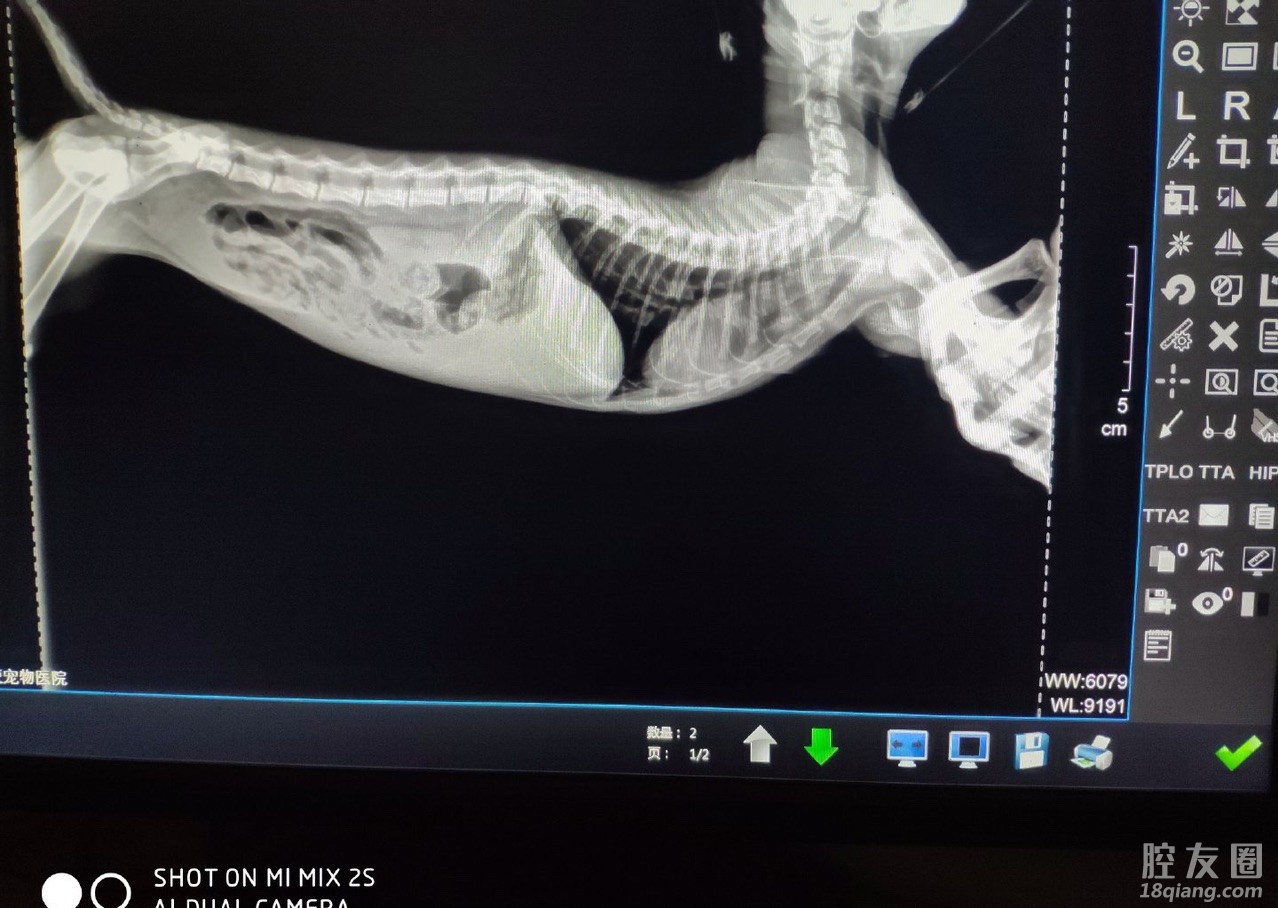

猫传腹到底是需要怎么治

昨天停针今天就发烧

441打了两个多月还是不见好

白蛋白有轻微升高 但未到正常值

贫血及肝肾功能有好转

有经验的宝宝能聊聊吗真的心急